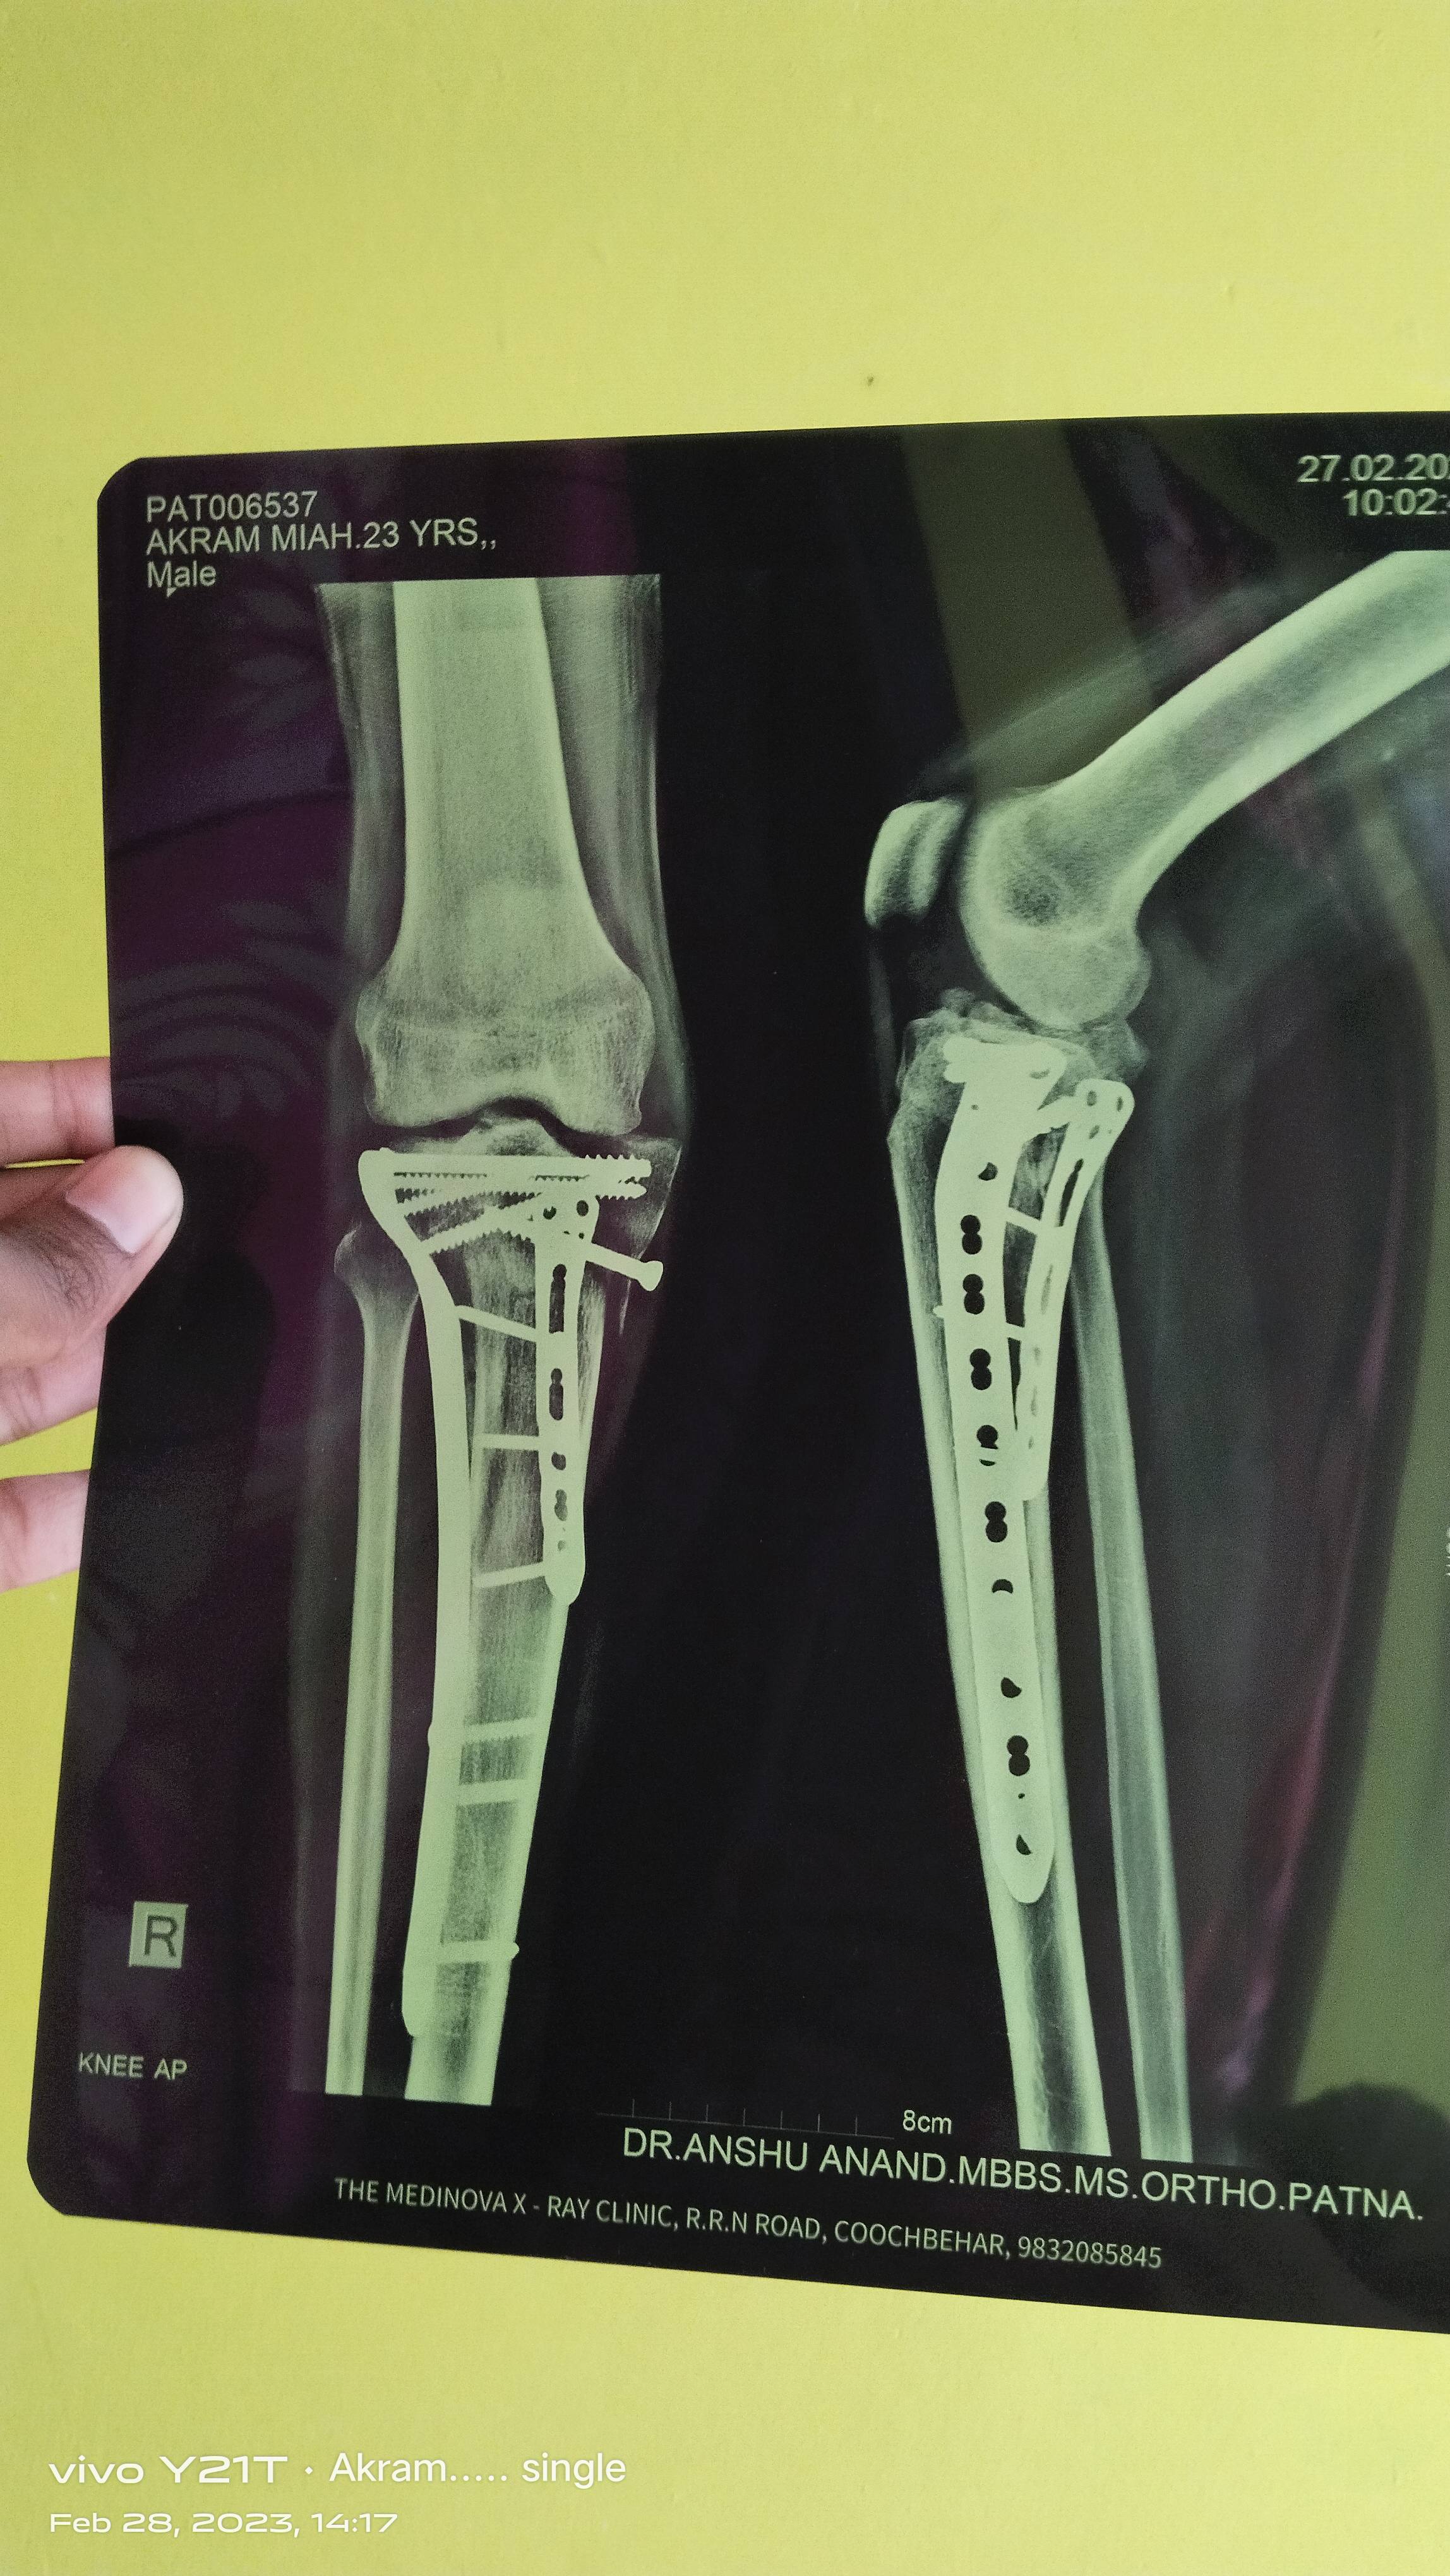

Akram mia